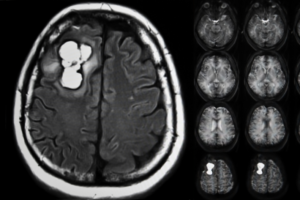

Beyin tümörü ameliyatı, iyi huylu ve kötü huylu beyin tümörlerinin tedavisinde en etkili ve en sık uygulanan yöntemdir. Meningiom, glial tümör (GBM), beyin metastazları ve diğer intrakraniyal kitlelerde cerrahi müdahale; tümörün tipine, yerleşimine ve hastanın nörolojik durumuna göre planlanır. Günümüzde gelişmiş mikrocerrahi teknikler, nöronavigasyon sistemleri ve uyanık beyin ameliyatı gibi ileri yöntemler sayesinde beyin tümörü ameliyatı daha güvenli ve başarılı şekilde gerçekleştirilmektedir.

Beyin tümörü ameliyatı süreci; tanı, ameliyat planlaması, cerrahi teknik seçimi, ameliyat sonrası takip ve olası ek tedavileri kapsayan çok aşamalı bir tedavi protokolüdür. Özellikle meningiom cerrahisi, glial tümör ameliyatı, Gamma Knife radyocerrahisi ve beyne metastaz yapan tümörlerin cerrahisi, hastalığın kontrol altına alınmasında kritik rol oynar.

Beyin metastazları, beynin en sık görülen tümörleridir ve genellikle primer tümörün başka bir organda gelişmesinin ardından tümör hücrelerinin kan dolaşımı yoluyla beyne yayılması sonucu ortaya çıkar. En sık akciğer kanseri, meme kanseri ve böbrek (renal hücreli karsinom) kaynaklı metastazlar görülür; daha nadiren melanom, kolorektal kanser veya tiroid kanseri gibi tümörler de beyne metastaz yapabilir. Beyin metastazlarının ortaya çıkışı çoğu zaman sistemik hastalığın ilerlemiş evresini gösterir.

Klinik olarak beyin metastazları tek bir odak şeklinde olabileceği gibi çok daha sık olarak birden fazla (multipl) lezyon şeklinde de ortaya çıkar. Bu çok odaklı yapı, hastanın nörolojik bulgularında ani kötüleşmeye, baş ağrısında artışa, epileptik nöbetlere veya denge–görme bozuklukları gibi fonksiyonel kayıplara yol açabilir. Lezyonların konumu ve sayısı, hastanın semptomlarının şiddetini doğrudan belirleyen faktörlerdir.

Beynin kendi hücrelerinden, yani glial hücrelerden köken alan tümörler, primer glial tümörler olarak adlandırılır. Bu tümörler; astrositler, oligodendrositler veya ependimal hücrelerden gelişebilir ve biyolojik davranışlarına göre düşük dereceli (grade I–II) ya da yüksek dereceli (grade III–IV) olarak sınıflandırılır. Glial tümörlerin klinik seyri oldukça değişkendir; tümörün hücresel tipi, genetik mutasyonları, büyüme hızı ve hastanın yaşı prognozu belirleyen en önemli faktörler arasındadır.

En agresif glial tümör tipi olan Glioblastoma Multiforme (GBM), Dünya Sağlık Örgütü (WHO) sınıflamasında Grade IV olarak tanımlanır. GBM, hızlı büyümesi, çevre beyin dokusuna yayılma eğilimi ve cerrahi sonrası mikroskobik kalıntılar bırakması nedeniyle tedavisi en zor beyin tümörlerinden biridir. Ayrıca MGMT promotor metilasyon durumu, IDH mutasyonu gibi moleküler belirteçler hastalığın gidişatında belirleyicidir. IDH mutasyonu pozitif olan hastalarda yaşam süresi belirgin şekilde uzayabilirken, bu mutasyonun bulunmadığı "IDH-wild type" GBM olguları genellikle daha kötü seyirlidir.